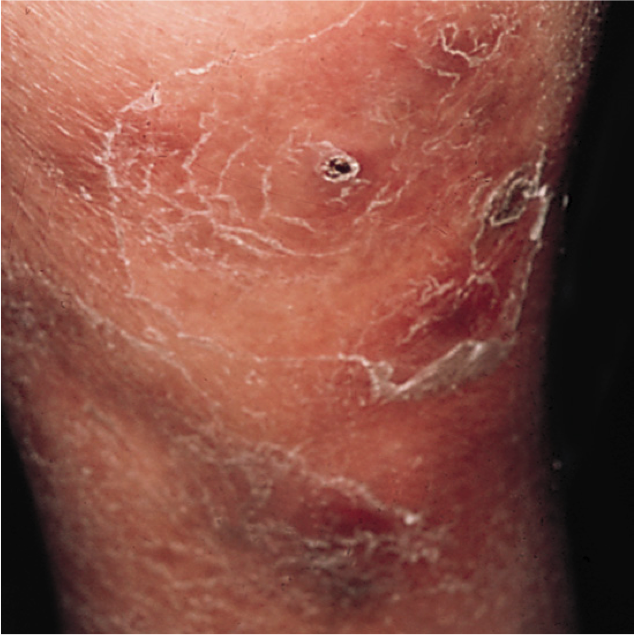

Localized Scleroderma

Plaque Morphea